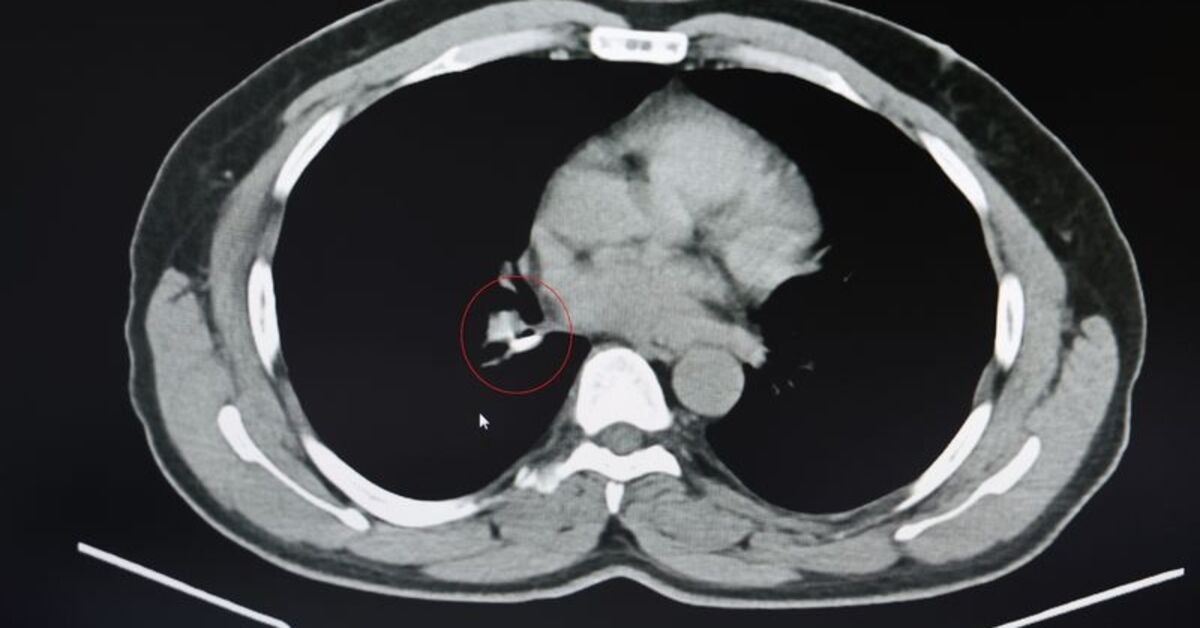

Şenyiğit, o maddenin zamanla akciğer yapısının özelliğini aldığını ve orada yabancı bir madde olarak kaldığına değinerek, “Hastamıza maalesef 2 yıldan beri astım tanısı konulmuş ve sürekli tedavi verilmiştir. Hasta bize geldiği zaman yapılan tomografide sağ akciğer ana bronşun distalinde şüpheli lezyon gördük. Uyguladığımız bronskokopide yabancı maddenin silikon olduğunu tespit ettik. Onu çıkardıktan sonra da hastada bir rahatlama meydana geldi” dedi.